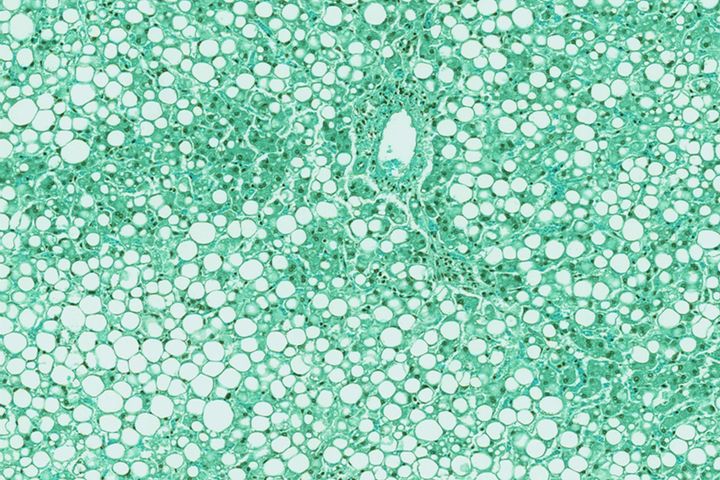

Liver cancer, also known as hepatocellular carcinoma (HCC), is a type of cancer that starts in the cells of the liver.

It typically develops after chronic inflammation leads to scarring (cirrhosis) of the organ. The most common causes of cirrhosis in Australia are alcohol-related liver disease, chronic hepatitis B and C, and non-alcoholic fatty liver disease. Over 80% of hepatocellular carcinomas occur in patients with cirrhosis.